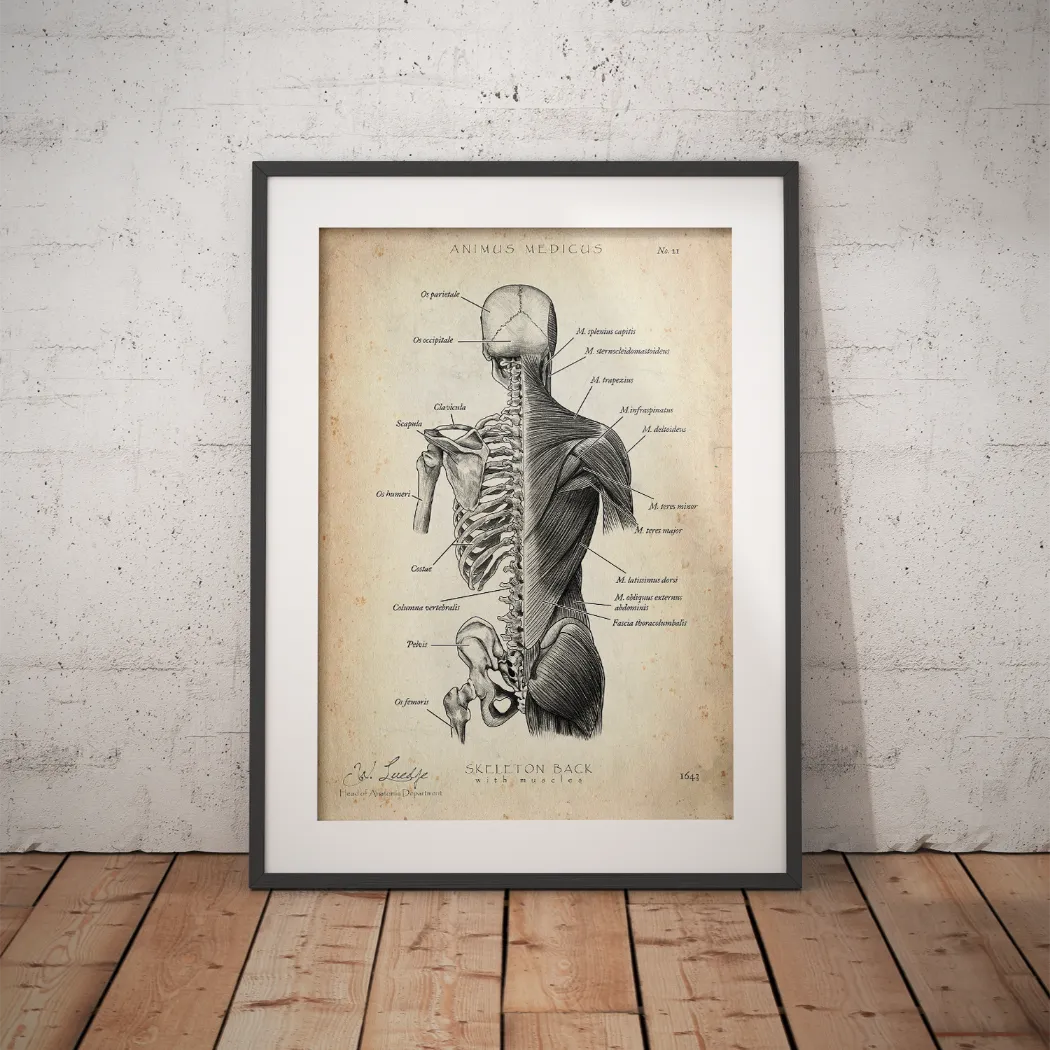

Warst du auf der Suche nach einer Möglichkeit, die faszinierende Anatomie des Herz-Kreislauf-Systems nicht nur zu lernen, sondern auch visuell zu erleben? Bei Animus Medicus findest du ästhetische Anatomie-Poster im Vintage-Stil, die medizinisches Wissen und kunstvolles Design perfekt vereinen. Entdecke jetzt unsere Kollektionen auf https://animus-medicus.de und bringe die Schönheit der Anatomie an deine Wände.